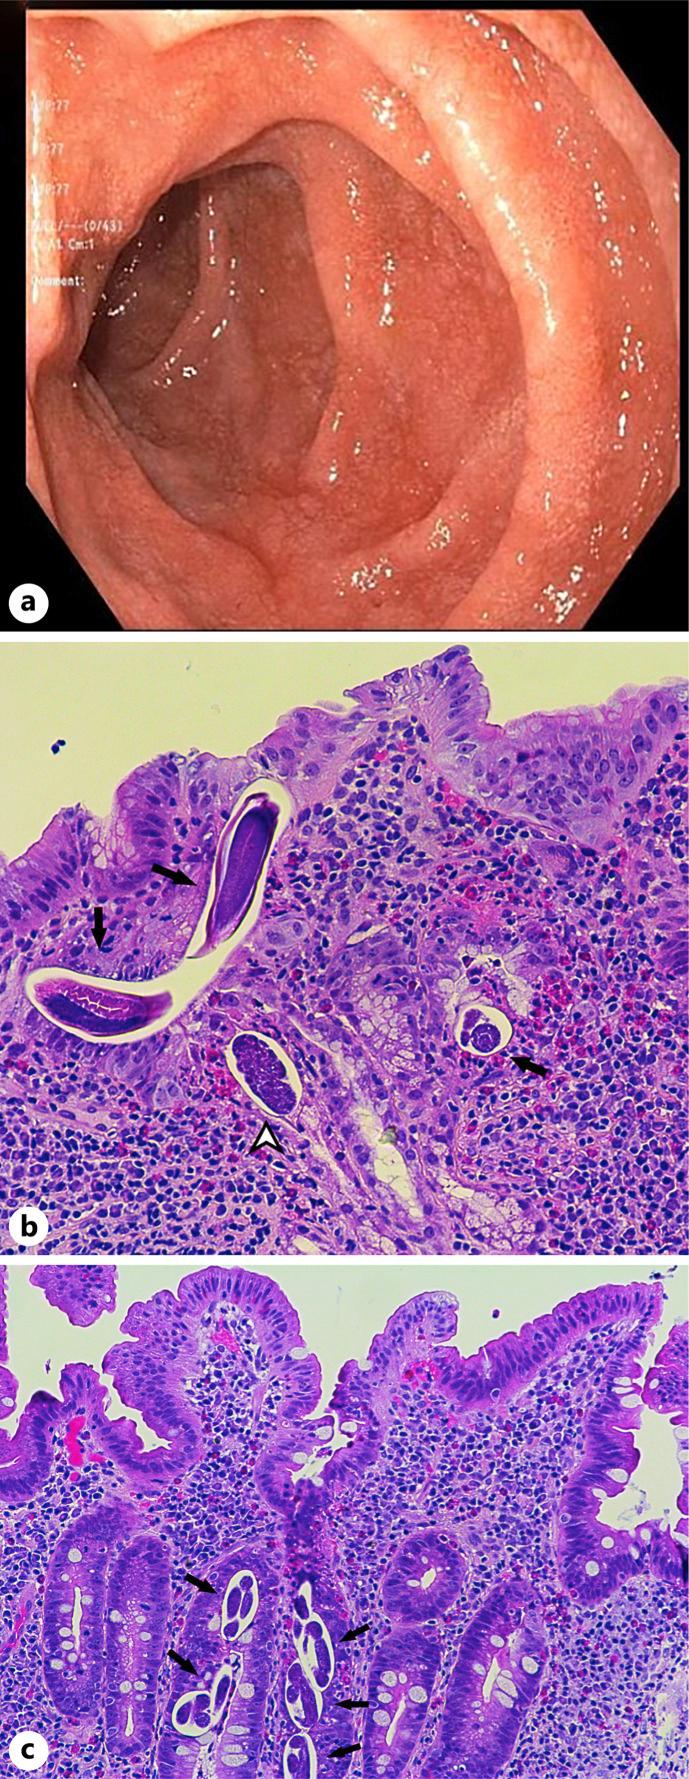

CASE PRESENTATION

In this case report, we describe the case of an asymptomatic and immunocompetent Liberian patient with gastroduodenal strongyloidiasis whose diagnosis was based on histologic findings during endoscopic evaluation for iron deficiency anemia.

在本病例报告中,我们描述了一例无症状且免疫功能正常的利比里亚患者,其患有胃十二指肠类圆线虫病,诊断基于缺铁性贫血内镜评估期间的组织学发现。